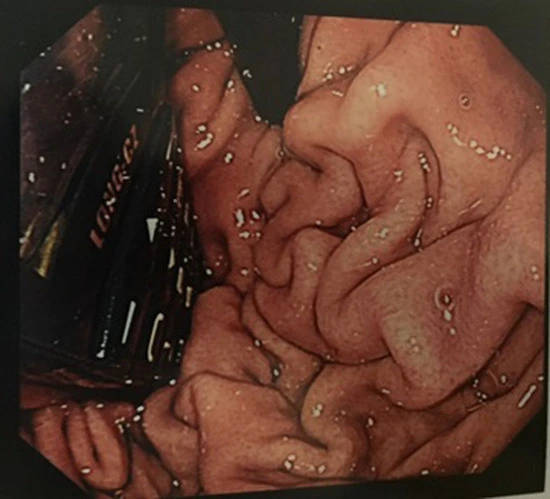

Niewielkie rozmiary urządzenia niestety niezbyt pomogły przy zabiegach lekarzy. Najpierw próbowano wyciągnąć telefon, przy ogólnym znieczuleniu, przez przełyk. Okazało się jednak, że może dojść do poważnego uszkodzenia gardła mężczyzny. Ostatecznie skończyło się na operacji żołądka, z którego to usunięto Long-Cz. Już w kilka dni po całej przygodzie 29-latek wrócił do więzienia, aby dalej odbywać swoją karę. Tym razem bez telefonu.